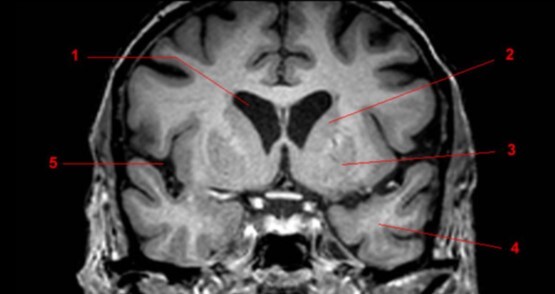

6

Q

Label 1-4

A

1. Lentiform nucleus

2. Caudate nucleus

3. Lateral ventricle

4. Cerebellum

7

1. Head of Caudate nucleus

2. Lateral ventricle

3. Thalamus